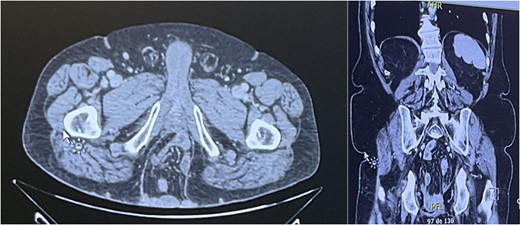

A computed tomography (CT) scan showed a PH of 9.5 × 8.7 × 15 cm, containing small bowel, with no sign of incarceration (Fig. 2). Given the symptomatic nature of the PH, a combined surgical procedure in collaboration with our plastic surgery team was planned.

CT scan revealing a PH of 9.5 × 8.7 × 15 cm, containing small bowel.